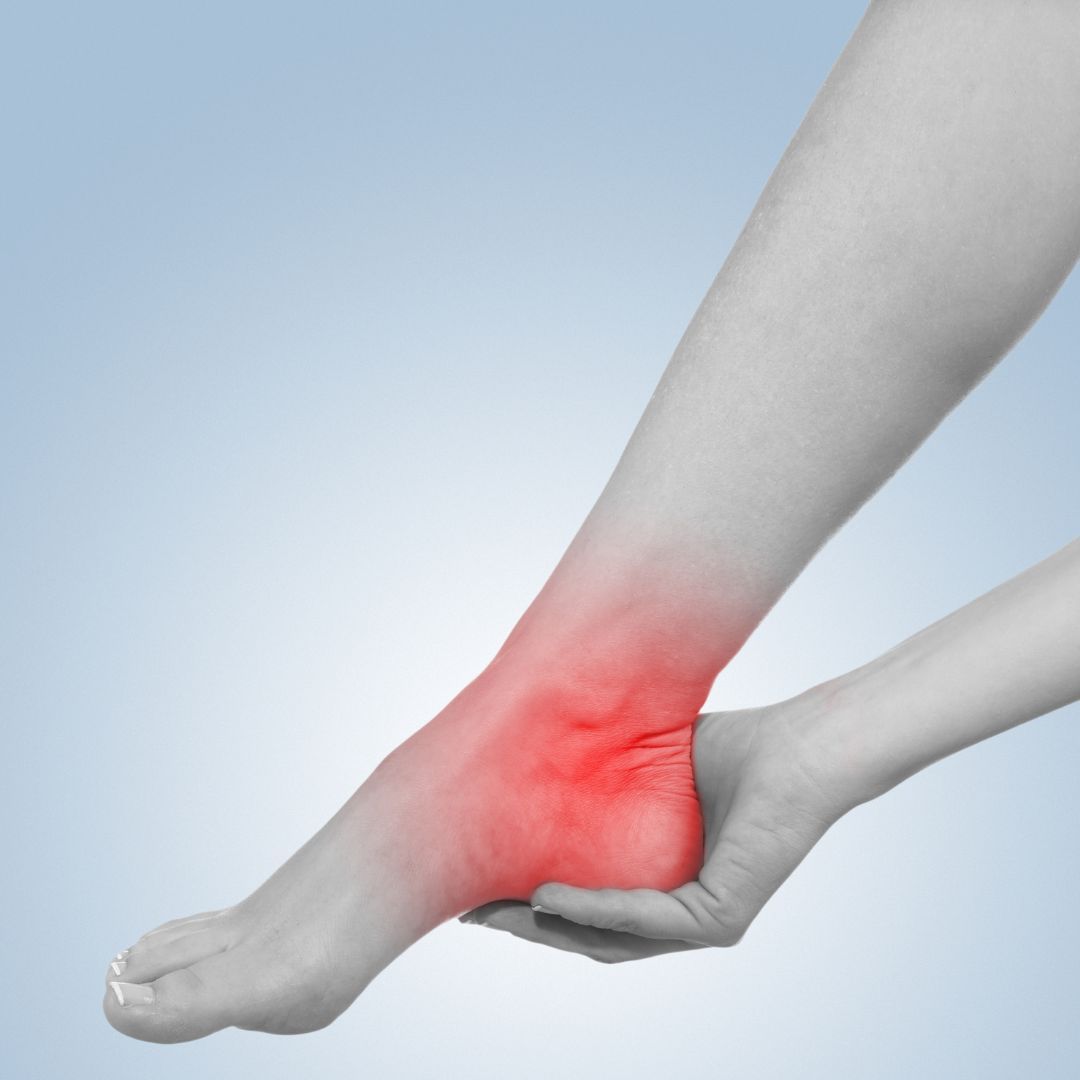

VALORACIÓN FUNCIONAL DE PIE Y TOBILLO

Las articulaciones de tobillo y pie soportan el peso total del cuerpo mientras generan el impulso de la marcha para realizar la deambulación, este es uno de los motivos por los que estas articulaciones se hallan expuestas a dolor y deformidades que forman parte de muchas lesiones y patologías como fracturas, luxaciones, caídas del arco, codroopatías, dedos en martillo, espolón calcáneo, fascitis plantar, bursitis, hallux, artrosis, esguinces, metatarsalgia, tendinitis, tendinosis, osteocondritis, etc.

En este taller repasaremos las pruebas funcionales que nos permitirán detectar muchas de las patologías y lesiones citadas.

Montse Herrero (fisioterapeuta y PNIE) para Master-D Barcelona

ESGUINCE DE TOBILLO / Vendajes

Una de las lesiones más frecuentes en el tobillo es el esguince de los ligamentos laterales externos. Esta lesión sucede habitualmente cuando caminando o corriendo sobre un terreno accidentado nos torcemos el tobillo traccionando los ligamentos que lo estabilizan.

En este taller aprederemos a detectarlo y practicaremos el vendaje funcional de soporte.

Montse Herrero (fisioterapeuta y PNIE) para Master-D Barcelona

TALALGIA / VALORACIÓN FUNCIONAL DIFERENCIAL

No todos los dolores de talón son fascitis, ni todos los esponlones se ubican en la misma zona del calcáneo.

En este taller veremos las diferentes patologías que cursan con dolor en el talón, así como también, los espolones más frecuentes que aparecen en el hueso calcáneo.

Montse Herrero (fisioterapeuta y PNIE) para Master-D Barcelona